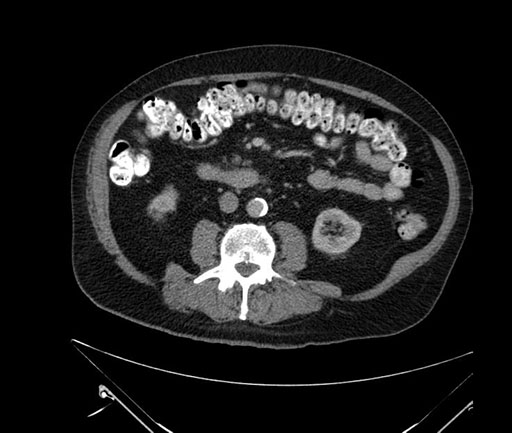

Whipple (pancreaticoduodenectomy) [case 7]

Imaging Analysis

Look through the patient's CT scan to identify any areas of concern for the necessary procedure.

Based on your CT findings, which issue(s) would give reason for "planned slowing down moment(s)" in this case?

Considering a standard Whipple procedure, what step(s) of the operation would you do differently in this case?